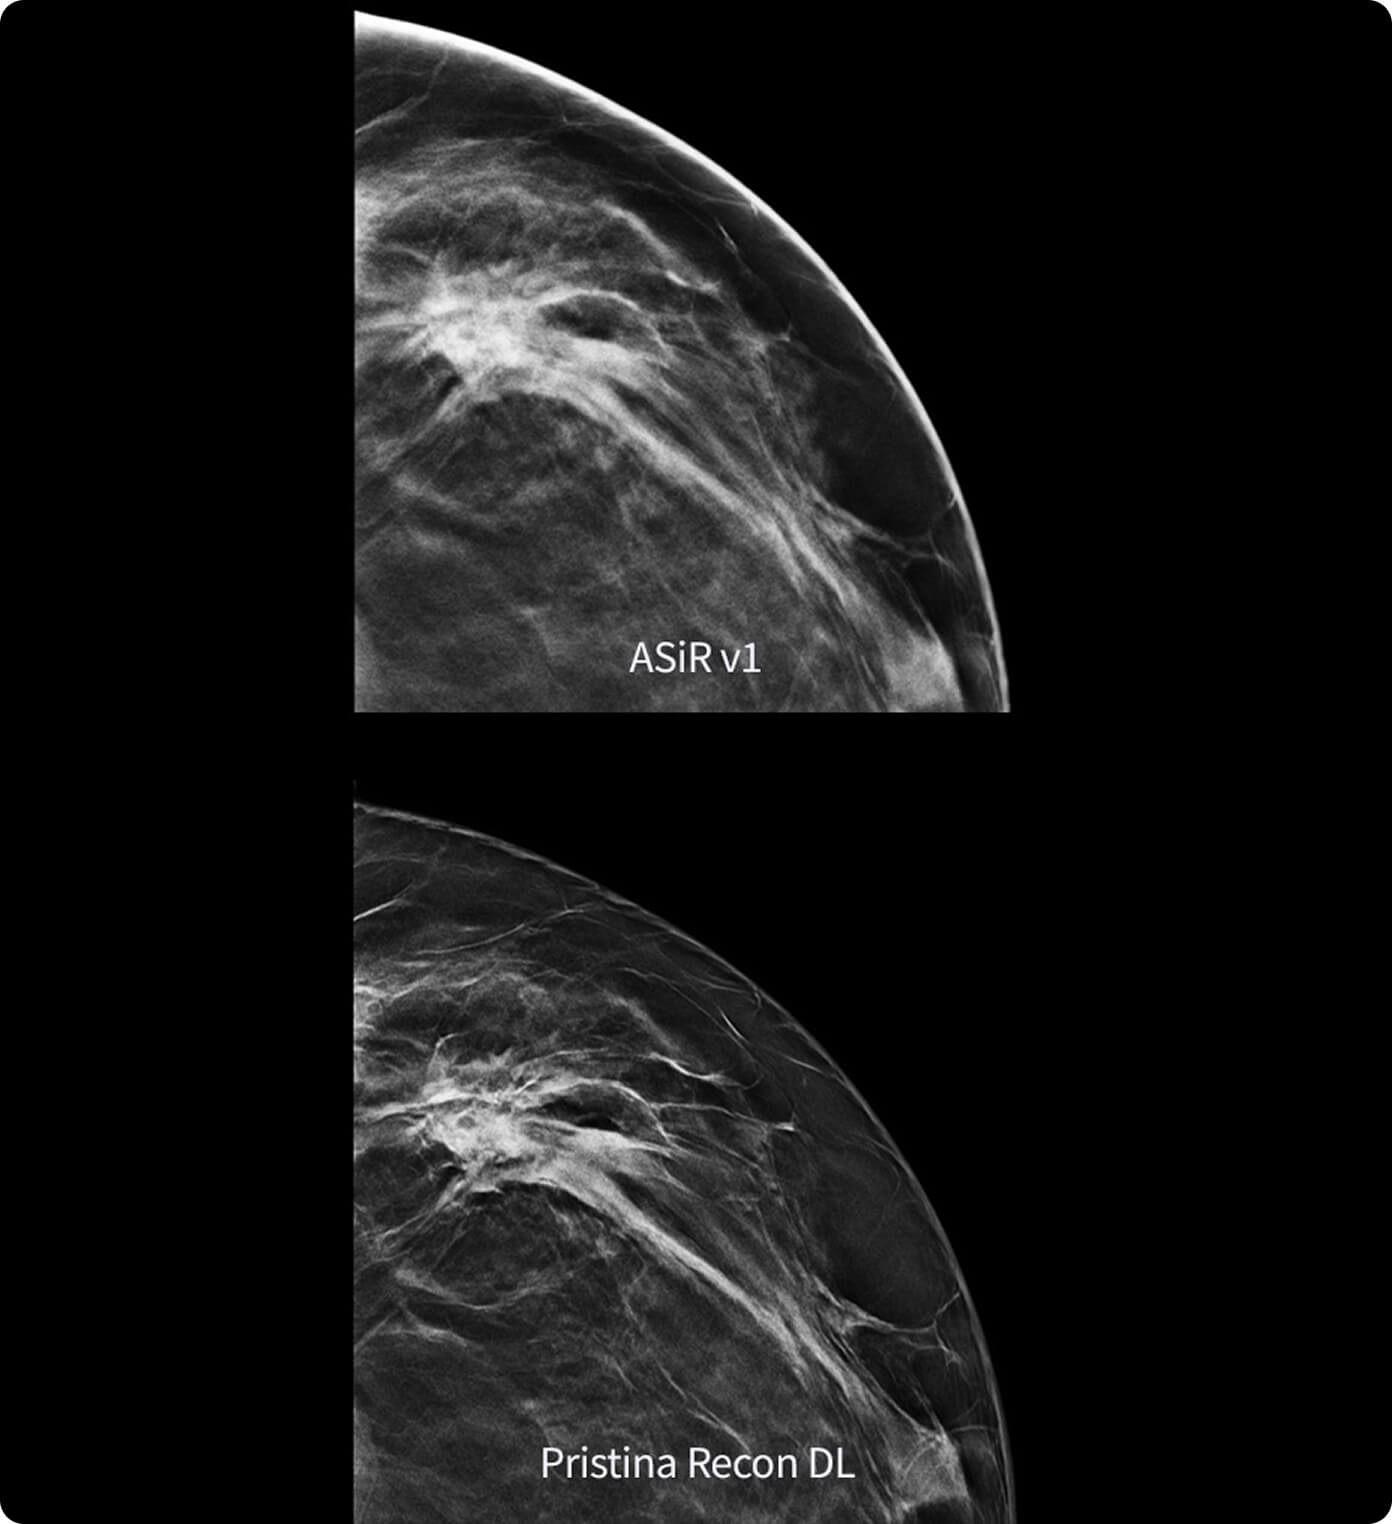

• Une qualité d'image exceptionnelle rendue possible par une largeur d'impulsion réduite et une puissance de crête inégalée pour la production des rayons X.

• Des détails impressionnants grâce à une large gamme de foyers proposés pour les modes d'acquisition scopie et ciné.

Unique set of capabilities to enhance system performance all along the image chain and optimize image quality and dose in real time automatically.